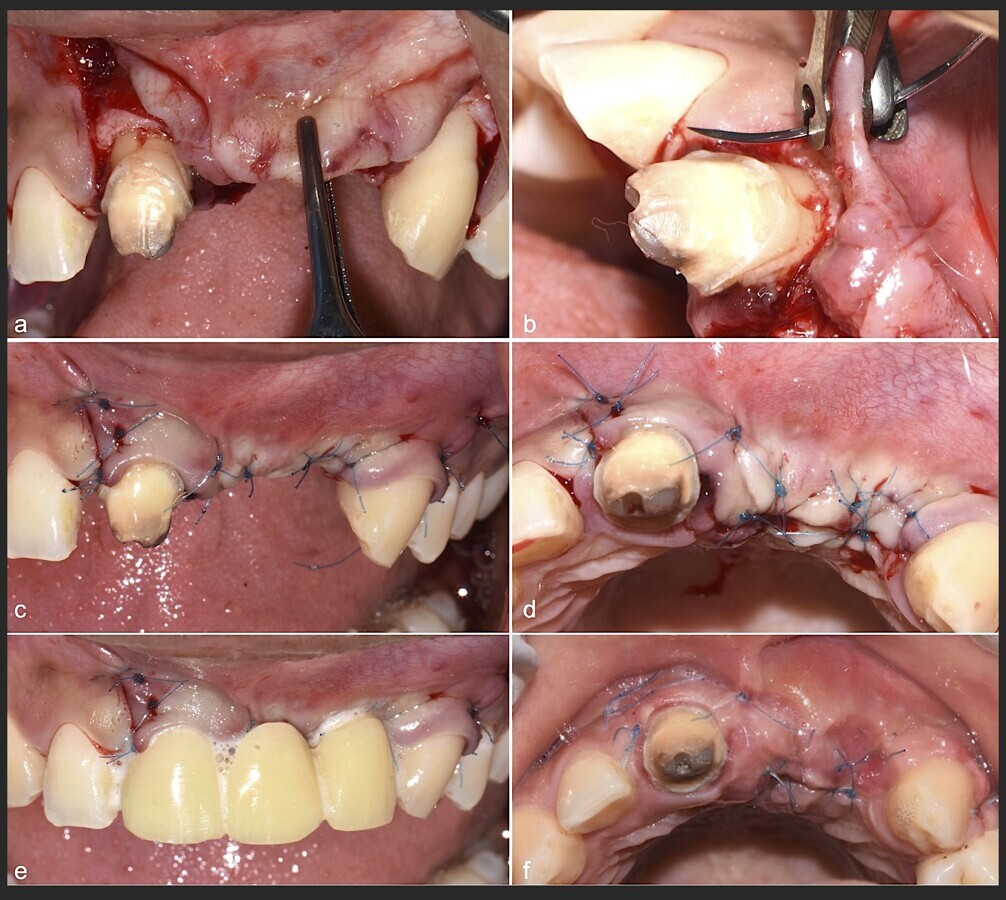

Figura 22. Liberación de colgajo y prueba de elasticidad del tejido blando (a) para un adecuado cierre sin tensiones y cicatrización por primera intención (b).

Figura 23. Imágenes de decorticalización de la zona receptora con brocas hasta llegar a la zona medular (a, b).

Figura 24. Imágenes de la verificación del sangrado proveniente de la zona medular (a, b).

Figura 35. Decolado a espesor total sobrepasando la línea mucogingival (a, b).

Figura 36. Defecto óseo y severa reabsorción ósea horizontal: vista clínica (a) y corte tomográfico (b).

Figura 37. Liberación del colgajo para asegurar un cierre sin tensiones.

Figura 38. Decorticalización por medio de broca de 1.2 mm de diámetro (a, b).

Figura 39. Uso del inserto plano de punta aserrado para realizar una mayor decorticalización (a). Surcos de vascularización y nutrición (b).

Figura 40. Secuencia de fijación y modelado del bloque óseo con inserto de corte, eliminación de ángulos agudos (a-d).

Figura 41. Modelado del bloque óseo con inserto plano de punta diamantada (a) para redondear los ángulos agudos y así evitar una dehiscencia o fenestración de los tejidos blandos (b).

Figura 42. El proceso de triturado de biomaterial óseo sustituto en bloque (a - d).

Figura 43. Colocación del biomaterial triturado (a - d).

Figura 44. Pasos para la colocación de la membrana de barrera (a - d).

Figura 45. Afrontamiento de colgajo y sutura (a - e). Control a los 7 días postquirúrgico (f).